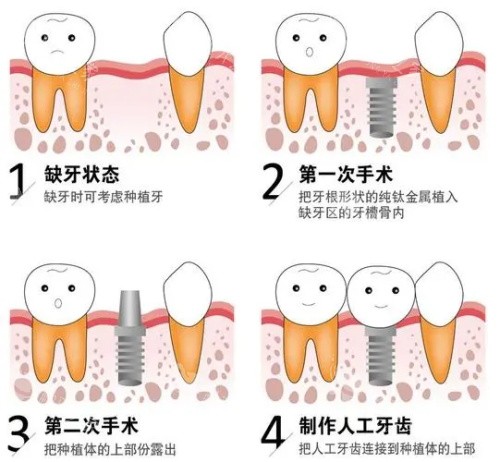

2026大连种植牙价格表更新,费用全透明!

在大连生活,缺牙后想种牙,比较担心的就是 “价格不透明,后续加钱”。好在 2026 年大连种植牙价格表全新更新,不管是国产种植体,还是进口种植体,从基础检查到比较终装牙冠,每一笔费用都列得清清楚楚。这次就带大家详细看看这份透明的价格表,再推荐一位靠谱的医生,听听三位患者的真实体验,帮你弄明白种牙到底要花多少钱,选哪家、找哪位医生更合适,让种牙这件事变得简单又放心。

种植牙类(高价项目):

国产种植牙(含基台 + 牙冠):3880 元起,适合单颗缺牙、预算有限的情况,耐用性能满足日常吃饭需求;

韩国进口种植牙:5580 元起,很多中年人会选,适应大部分人的牙槽骨条件,咀嚼力不错;

德国进口种植牙:7780 元起,适配性强,就算牙槽骨有点薄,也能在医生指导下种植;

瑞士进口种植牙:9780 元起,对精度要求高,长期使用稳定性好,适合追求长期结果的人;

在大连一家口碑不错的私立口腔医院里,赵阳医生是很多人种牙时的首要选择。他做种植牙快十年了,不管是简单的单颗种植,还是复杂的半口种植,都能耐心对待。头一次找他面诊,他不会直接推荐贵的种植体,而是先带你做口腔 CT,指着屏幕说:“你这牙槽骨条件不错,选国产种植体就够用”“这里有点凹陷,得稍微调整下种植角度”,把特色的事情说得通俗易懂。